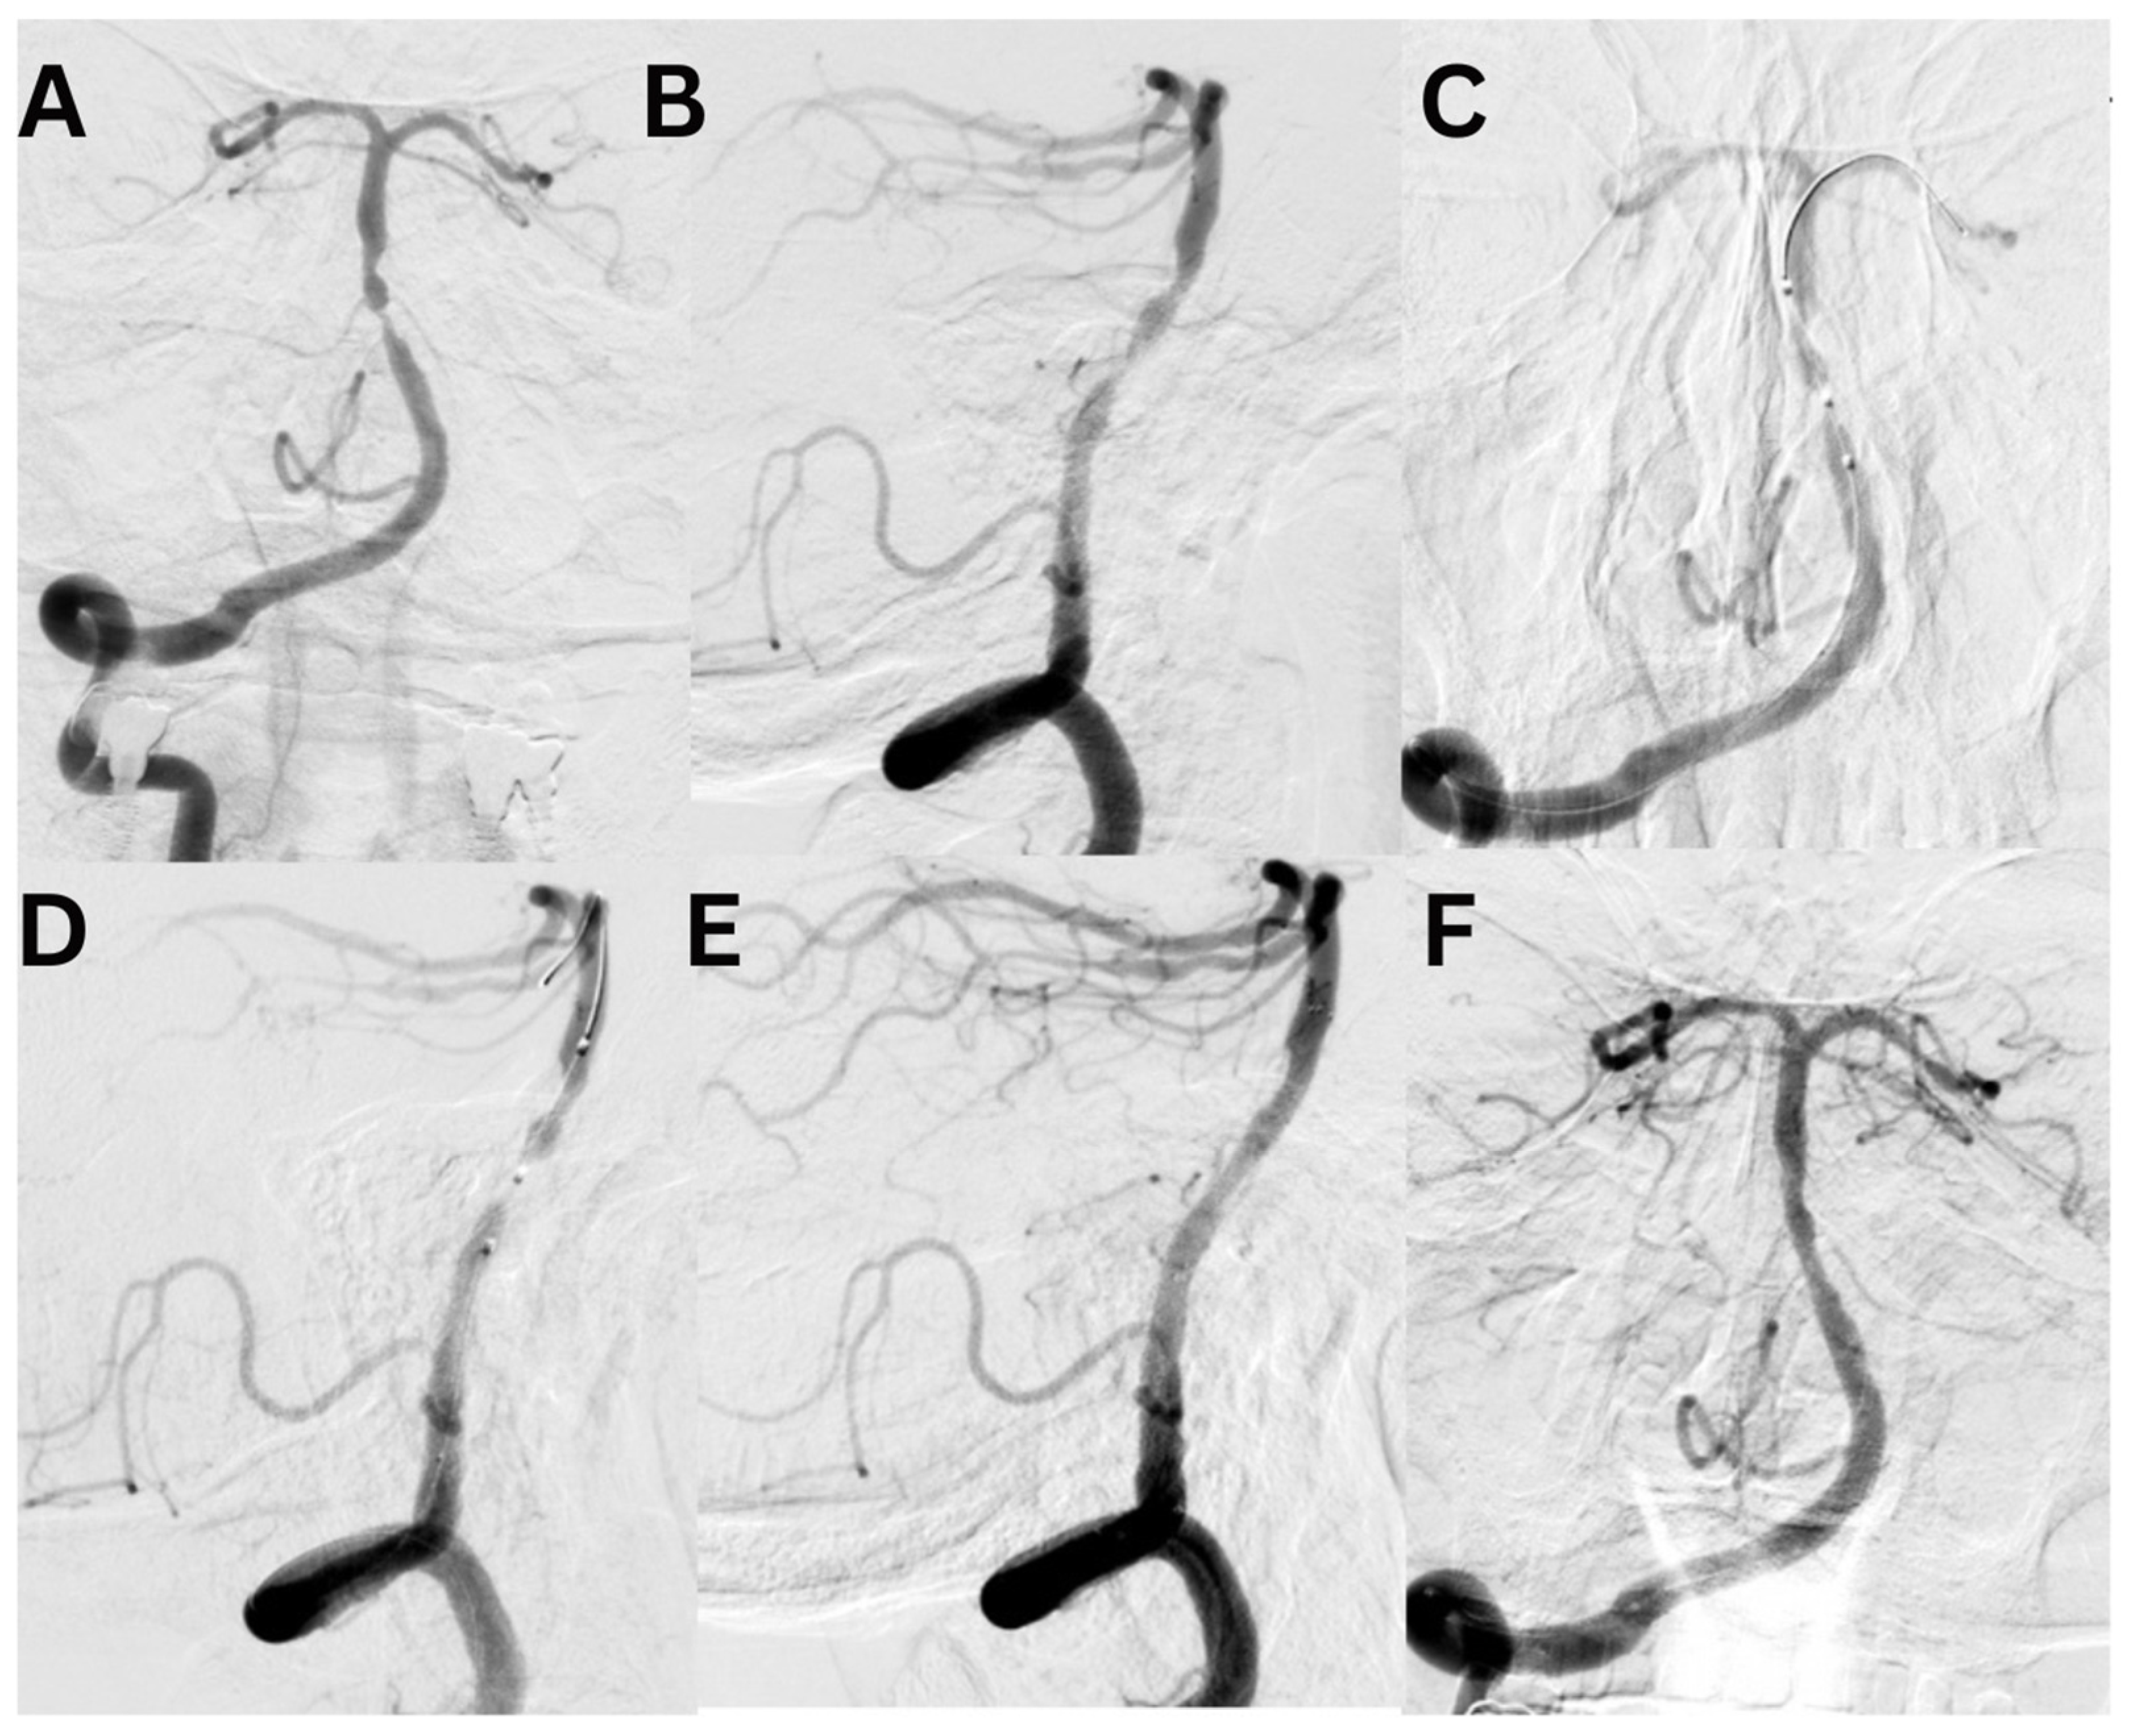

Case #2. A 48-year-old male patient presented with persistent pulsatile sensation in the parietal region, tinnitus, dizziness, blood pressure instability, right-sided weakness, general weakness, decreased work capacity, sleep disturbances, and memory loss. The patient had a history of hypertension for over 10 years and had experienced an ischemic stroke in the left middle cerebral artery territory two months prior, which was managed conservatively. Magnetic resonance imaging revealed signs of chronic ischemia in the right parietal and temporal lobes with cystic-gliotic changes, as well as single foci of hemosiderin deposition in the white matter of the cerebral hemispheres and basal ganglia, likely indicating microhemorrhage in the chronic stage. The patient underwent a comprehensive evaluation by a multidisciplinary team, including a cardiologist, neurologist, and pharmacologist, and was subsequently placed on ticagrelor. The procedure was performed under local anesthesia. An 8 French introducer was placed in the right femoral artery, and 8 French Hyperion catheters were navigated and positioned in the left internal carotid artery, covering the area of dissection and stenosis. DSA revealed a left M1 segment stenosis (Figure 5A,B). An Asahi Chikai Black 0.014 microwire was then advanced and placed in the M2 segment of the left middle cerebral artery. A dual-lumen coaxial microcatheter, the NeuroSpeed 2.0 × 8.0 mm, was navigated to the stenotic region and inflated twice using an inflator, resulting in a residual stenosis of up to 40%. Next, during the attempt to deploy an Acclino Flex 5.0 × 20 mm stent through a balloon catheter starting from the M1 bifurcation of the left middle cerebral artery, the proximal portion of the stent became fixed within the balloon catheter due to the radiopaque markers. As a result, the balloon microcatheter and the damaged stent were removed (Figure 5C). Subsequently, a GAMA 17 catheter was navigated through the Asahi Chikai Black 0.014 microwire, and an intravascular Acclino Flex 5.0 × 20 mm stent was reinserted and deployed to eliminate the stenosis (Figure 5D). The final angiographic evaluation demonstrated a patent left middle cerebral artery without any residual narrowing (Figure 5E,F).

Figure 5. A diagnostic cerebral angiogram demonstrates an 80% stenosis of the right MCA (A,B) in a patient who presented with recurrent TIAs as evidenced by left-sided weakness/numbness. A diagnostic cerebral angiogram performed after stent placement and angioplasty demonstrates (C,D) resolution of stenosis. The operation was performed with an Acclino stent (E,F).